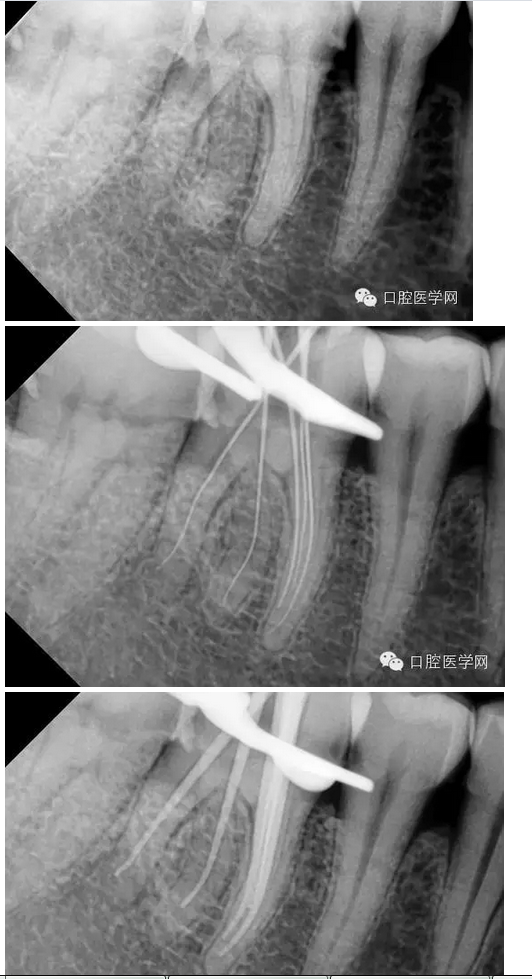

下六五根管治療一例

患者:男,44歲

主訴:右下后牙進(jìn)食痛2周,加重2天。

現(xiàn)病史:牙齒有洞,無不適,未處理,2周前開始進(jìn)食痛,口服消炎藥,好轉(zhuǎn),2天前晚上劇烈疼痛,今來看診。

檢查:#46牙頰側(cè)小洞,探(++),叩(-),冷熱(+++),咬頜正常,牙齦未見不適,未見其它不適。

診斷:#46牙髓炎

治療計(jì)劃:#46根管治療+冠修復(fù)保護(hù)。